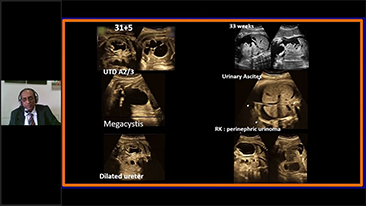

Foetale urineanomalieën

Aangeboren afwijkingen van de foetale nieren en urinewegen